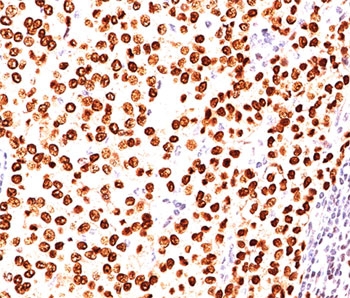

This antibody is specific to progesterone receptor and shows minimal cross-reaction with other members of the family. Progesterone receptor is expressed as two major isoforms, PR-A (81kDa) and PR-B (116kDa). Expression of progesterone receptor has been suggested to reflect a intact estrogen regulatory machinery and therefore predict better clinical response to endocrine therapy than ER alone. This progesterone receptor antibody is excellent for immunohistochemical staining of formalin/paraffin tissues.

1. Staining of formalin-fixed tissues requires boiling tissue sections in pH 9 10mM Tris with 1mM EDTA for 10-20 min followed by cooling at RT for 20 minutes.

2. The prediluted format is supplied in a dropper bottle and is optimized for use in IHC. After epitope retrieval step (if required), drip mAb solution onto the tissue section and incubate at RT for 30 min.